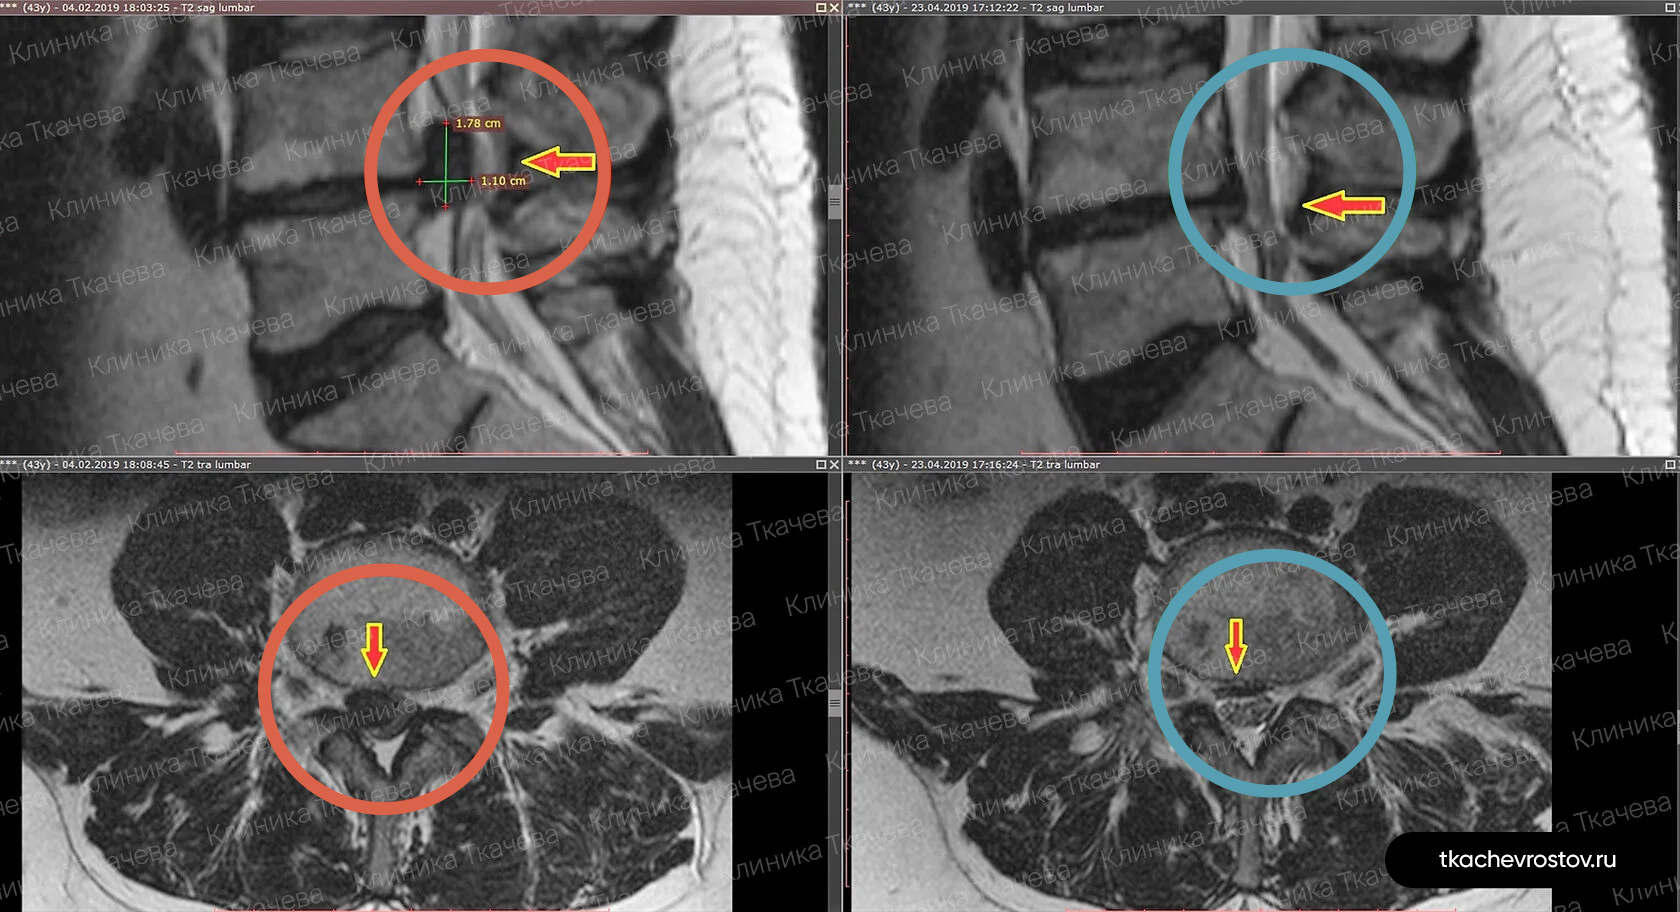

Лечение грыжи в шейном отделе C6-C7

Грыжа в шейном отделе C6-C7

Женщина. Грыжа в шейном отделе C6-C7 1.8х0.8см. Из-за боли передвигалась по стеночке. Отказалась от операции по квоте – замена диска на имплант.

ДО:

- Больно дышать и говорить

- Какие-либо движения головы приносили жуткую боль

- Правая рука не слушалась, частично онемели ладонь и пальцы руки

- Обезболивающие, блокады, капельницы. Ничего не помогло

- Потеря трудоспособности и ограничение жизнедеятельности

ПОСЛЕ 1 курса:

✓ Наступила резорбция грыжи

✓ Наступило улучшения общего состояния

✓ Стала лучше работать правая рука

✓ Ушло частичное онемение

✓ Голова стала поворачиваться во все стороны

✓ Ушла выраженная боль и напряжение в шее

✓ Пациентка смогла сесть за руль

ПОСЛЕ 2 курса:

✓ Полная резорбция грыжи

✓ Восстановление всех двигательных функций

✓ Прекрасное самочувствие

Всё лечение заняло полгода (2 курса по 15 дней).